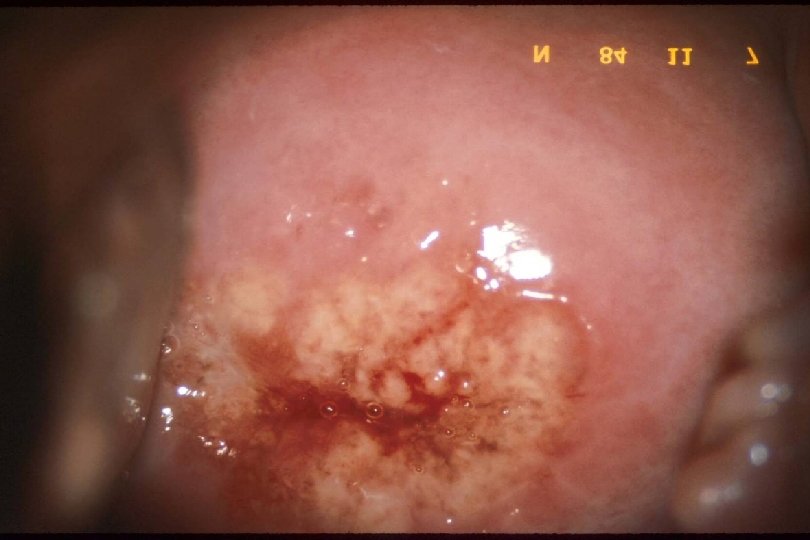

The Cervix and Trichomoniasis l Classic: “strawberry cervix” Ø Focal areas of superficial hemorrhage surrounded by paler mucosa Ø May also see more subtle petechiae Ø More common with relatively moderate-severe Trichomonas vaginitis

Cervicitis due to Trichomonas vaginalis

STD as a Cause of Cervicitis · · · Endocervicitis (mucopurulent cervicitis, MPC) - Gonorrhea Chlamydia ? Mycoplasma genitalium Other/unknown Ectocervicitis: often associated with vaginal infection - Trichomoniasis Candida albicans (probable but infrequent) Bacterial vaginosis (? ) Discrete lesions - Herpes simplex virus (and other ulcerative agents) Syphilis Human papillomavirus Cervical cancer